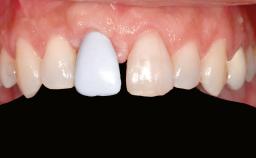

Shell Technique for Horizontal and Vertical Maxillary Bone Augmentation in a Partially Edentulous Patient with Aggressive Periodontal Disease

A 46-year-old woman was referred for treatment whose main complaints were mobility of her fixed partial dentures (right maxilla and left mandible) and periodontal bleeding during function. She also reported having taken systemic antibiotics to treat recurrent swelling in the area of the upper left molars. The patient had not seen a dentist for at least 2 years. She did not smoke and had no history of major systemic disease other than two minor orthopedic procedures some years back. The first-visit examination revealed poor plaque control, tooth mobility, periodontal disease, and a residual dentition widely associated with deep periodontal pockets.

Prosthesis Type FDP

Defining Characteristics Up to three missing teeth to be replaced with an implant-borne restoration or restorations